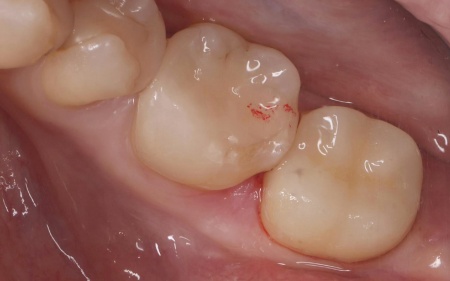

| 行ったご提案・治療内容 | 患者様は審美性と長期間使用できる耐久性を重視されていたため、従来の小さなインレータイプではなく、より広い範囲で歯の噛む面全体を覆うオンレータイプでの修復治療を提案しました。

メリット:被せ物の面積が広く、噛む力によって生じる負担を分散できるため、欠けや破折を予防できる メリットとデメリットを丁寧にお伝えしたところ、オンレータイプの被せ物による治療に同意いただきました。 まず、破折した既存のセラミックインレーを慎重に除去します。 オンレーに用いる素材は、強度と自然な見た目を兼ね備えたE-MAX(イーマックス)を選択しました。 後日、完成したオンレーを装着して噛み合わせを丁寧に整え、見た目や使用感に問題がないことを確認し、治療を終了しました。 |

治療後